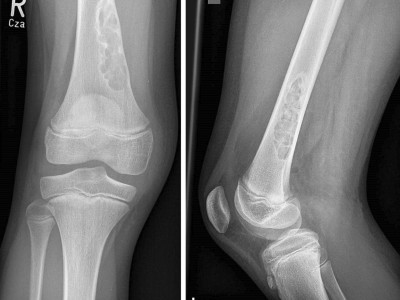

Schmerzbedingt kann ein 15-Jähriger sein rechtes Knie nur eingeschränkt bewegen. Seit etwa 3 Monaten verschlechtert sich die Symptomatik, insbesondere beim Sport. ASS bringt keine Besserung. Welche Diagnose stellen Sie? Zur Wahl stehen eosinophiles Granulom, Riesenzelltumor, Chondroblastom, Osteoidosteom, Osteomyelitis.